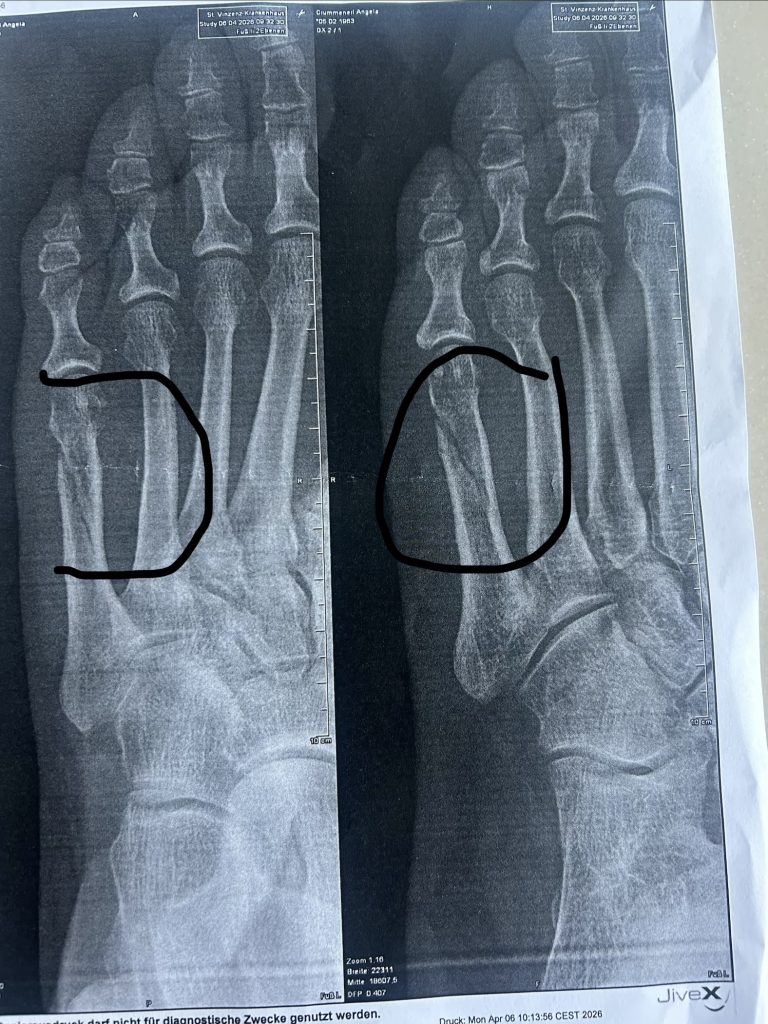

Am Abend vor unserer Abreise nach Sylt stand ich noch auf einer Trittleiter. Einen Moment später lag ich am Boden – mit gebrochenem Fuß. Nach drei Lungenentzündungen in kurzer Zeit fühlte es sich an, als würde mein Körper mir erneut Grenzen setzen. Doch am nächsten Morgen saß ich trotzdem im Auto Richtung Sylt.

Am letzten Abend zu Hause, kurz vor der Abreise, passierte es: Ich stürzte von einer Trittleiter und brach mir den Fuß. In diesem Moment war da erst einmal nur Schock, Schmerz und die große Frage: Soll ich die Reise absagen?

Nach allem, was hinter mir lag, fühlte sich dieser Unfall wie ein weiterer Rückschlag an. Drei Lungenentzündungen – und nun auch noch ein gebrochener Fuß.